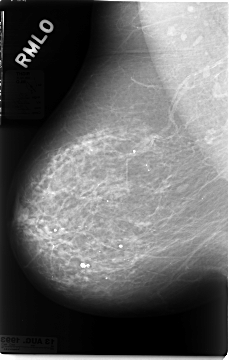

C_0028_1.RIGHT_MLO

RIGHT_CC LINES 4664 PIXELS_PER_LINE 2832 BITS_PER_PIXEL 12 RESOLUTION 50 NON_OVERLAY

RIGHT_MLO LINES 4672 PIXELS_PER_LINE 2976 BITS_PER_PIXEL 12 RESOLUTION 50 NON_OVERLAY